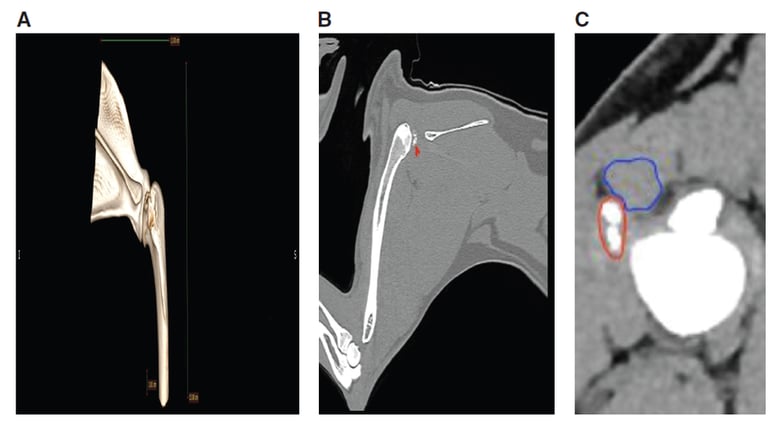

- CT

CT

OncologyCongenitalNeurologyGastrointestinalProcedureAnatomyDermatologyFarm AnimalHepatobiliaryArtificial IntelligenceGenitourinaryMusculoskeletalCanineThrowback ThursdayMust Know PaperCardiovascularAvian/ExoticsEquineUltrasoundNuclear MedicineFelineRadiographyDentistryInfectiousEndocrinologyMRICTVascularHematologyRespiratory